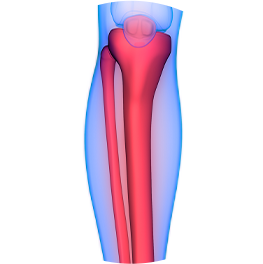

神経の位置

神経の深さ

筋肉の厚さ

血管分布

筋膜構造